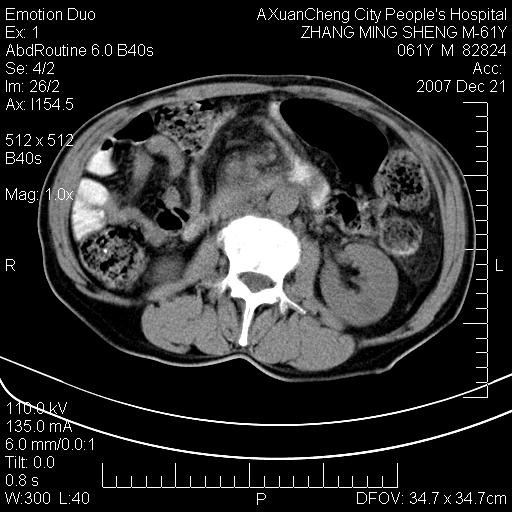

标题: CT11031:M61Y,胰腺占位 [打印本页]

标题: CT11031:M61Y,胰腺占位

大家侃侃门静脉和胆管系统怎么回事,肝内转移?

2,肝内多发结节状低密度占位,伴门脉及肠系膜上v栓子形成.考虑a;门脉及肠系膜上v血栓后肝改变.b;弥漫型肝癌伴门脉及肠系膜癌栓.

肝硬化,门脉高压,脾肿大;弥漫性肝癌,肝内、门脉、腹膜后淋巴结转移,肝内外胆管扩张,胰头区占位,建议mr检查

胰腺癌伴肝内转移;门脉、肠系膜上v癌栓形成。

考虑为:胰腺癌伴肝脏转移、腹膜后淋巴结转移,门静脉及肠系膜上静脉瘤栓形成。

胰体尾癌伴肝内转移,门静脉及肠系膜上静脉瘤栓形成.